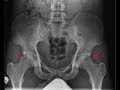

Femoroacetabular Impingement (FAI)

This is a patient with bilateral hip pain. A frontal radiograph of the pelvis and hips was obtained with demonstrate small osseous bumps at the femoral head and neck junctions bilaterally as indicated by the red arrows. There is subtle radiolucency underlying these osseous bumps which is referred to as fibrocystic changes. These constellation of findings can be seen with femoracetabular impingement, abbreviated as FAI, specifically cam-type FAI. These small bumps may impinge on the roof of the acetabular roof with movement leading to hip pain, labral tears, and progression to osteoarthritis.